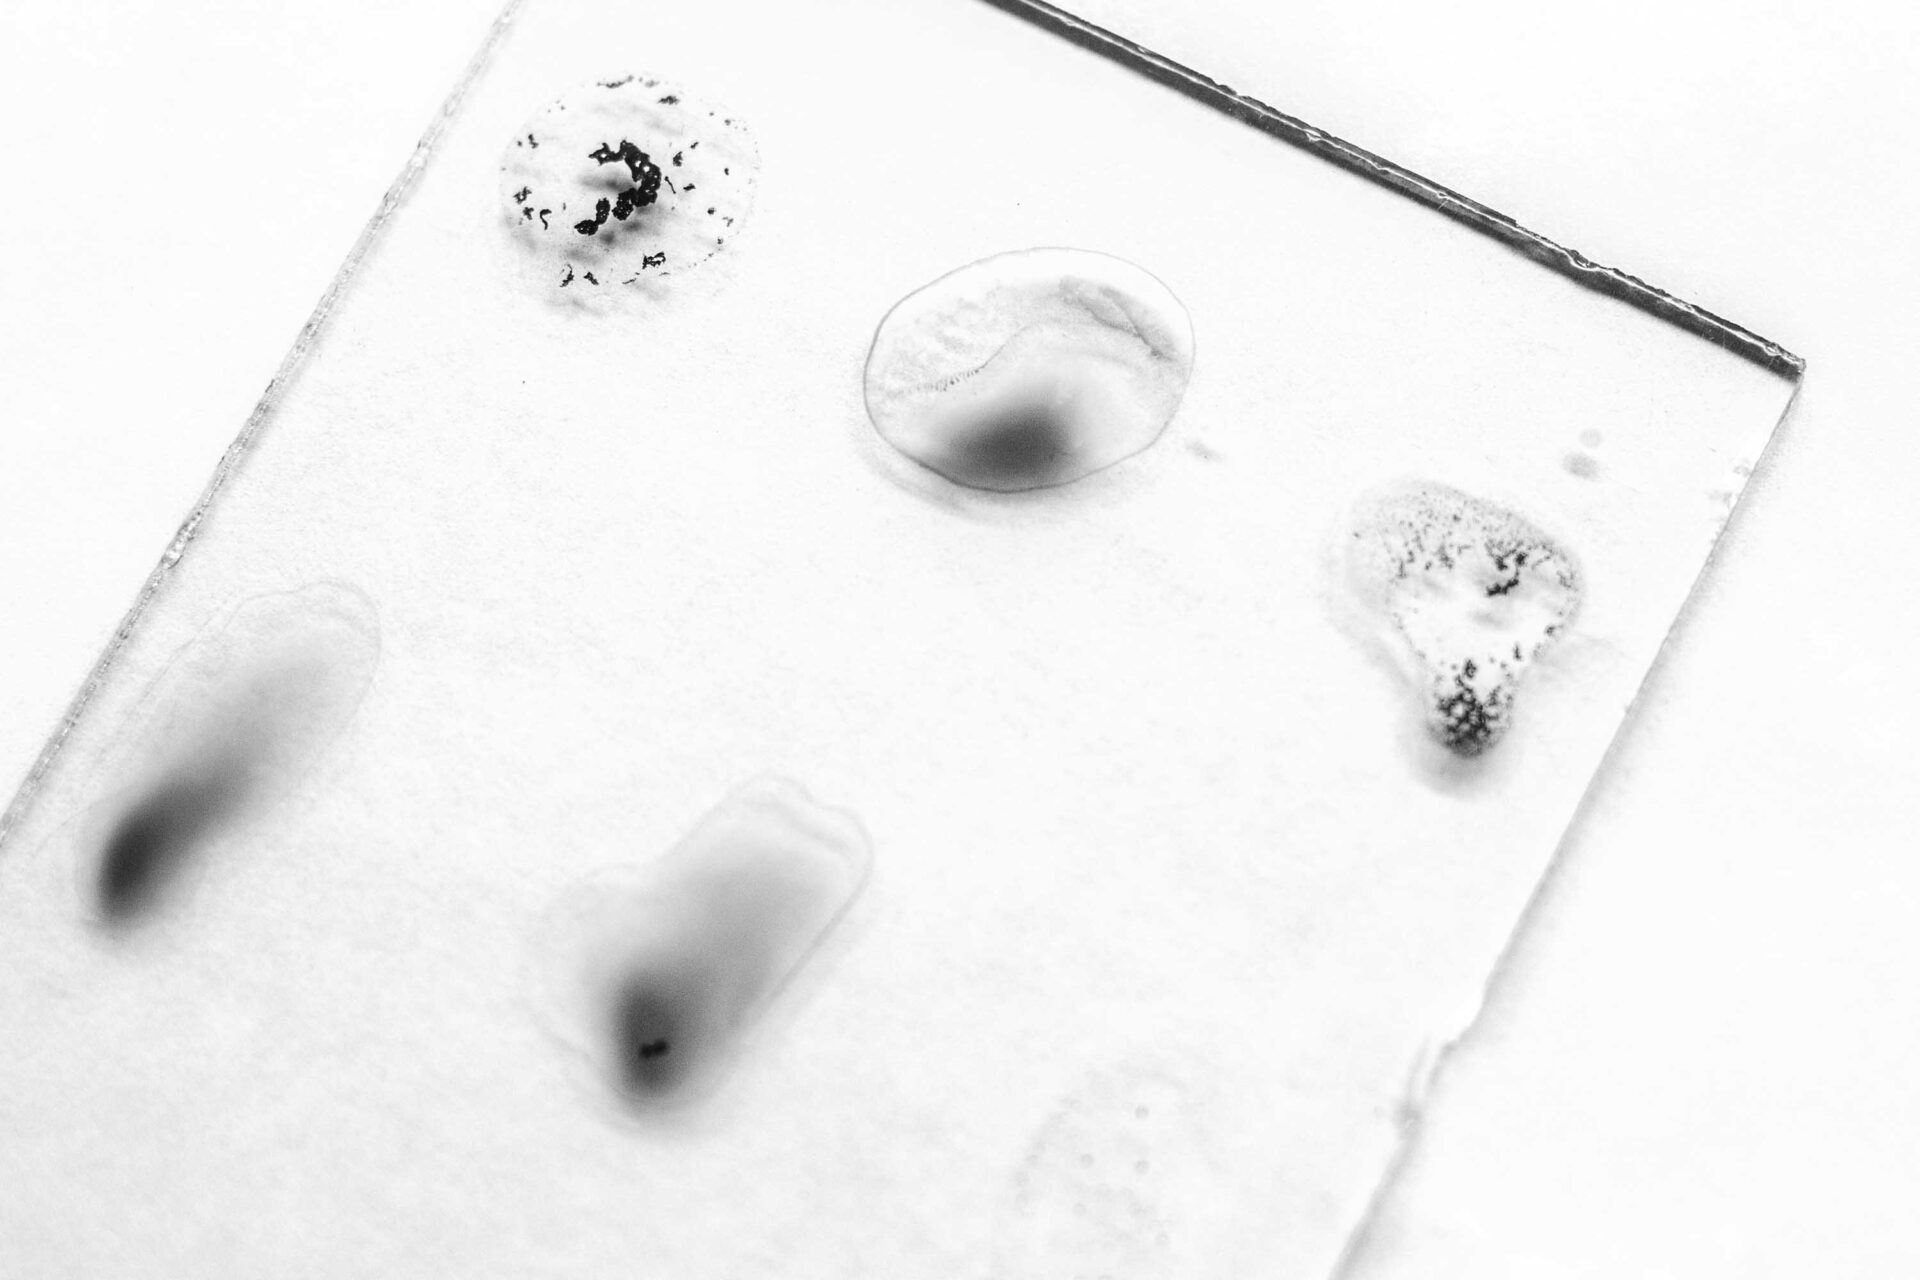

Chagas disease is an infection caused by a Trypanosoma cruzi (T. cruzi) parasite. Although it usually does not present symptoms, in 3 out of 10 people it can cause complications in the heart and digestive system. The transmission can be vectorial, -through the vinchucas or bed bugs infected with the parasite-, or vertical transmission -from the pregnant mother to her children-.